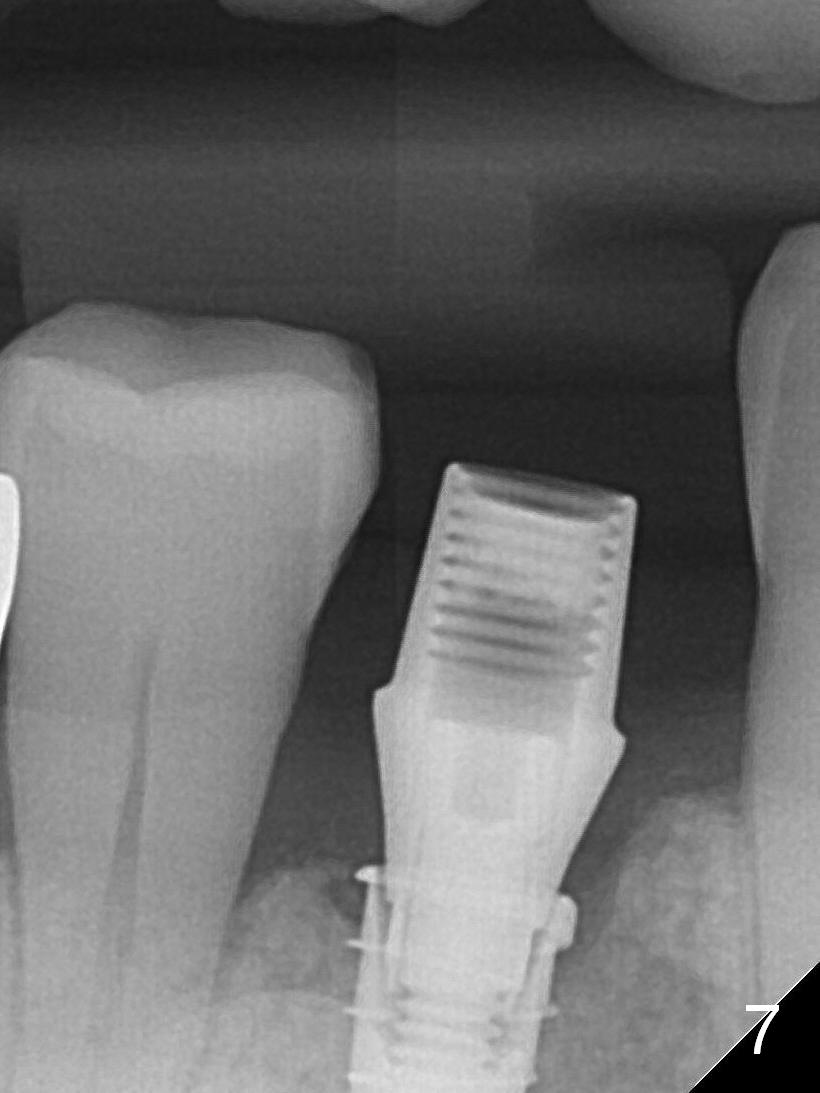

After placement of a 4x11 mm implant, a 4.5x4(2) mm abutment is inserted (Fig.4). Three months postop (Fig.6,7 (incomplete abutment seating (hand tightening))), the implant is loaded for intrusion of the opposing supraerupted tooth.